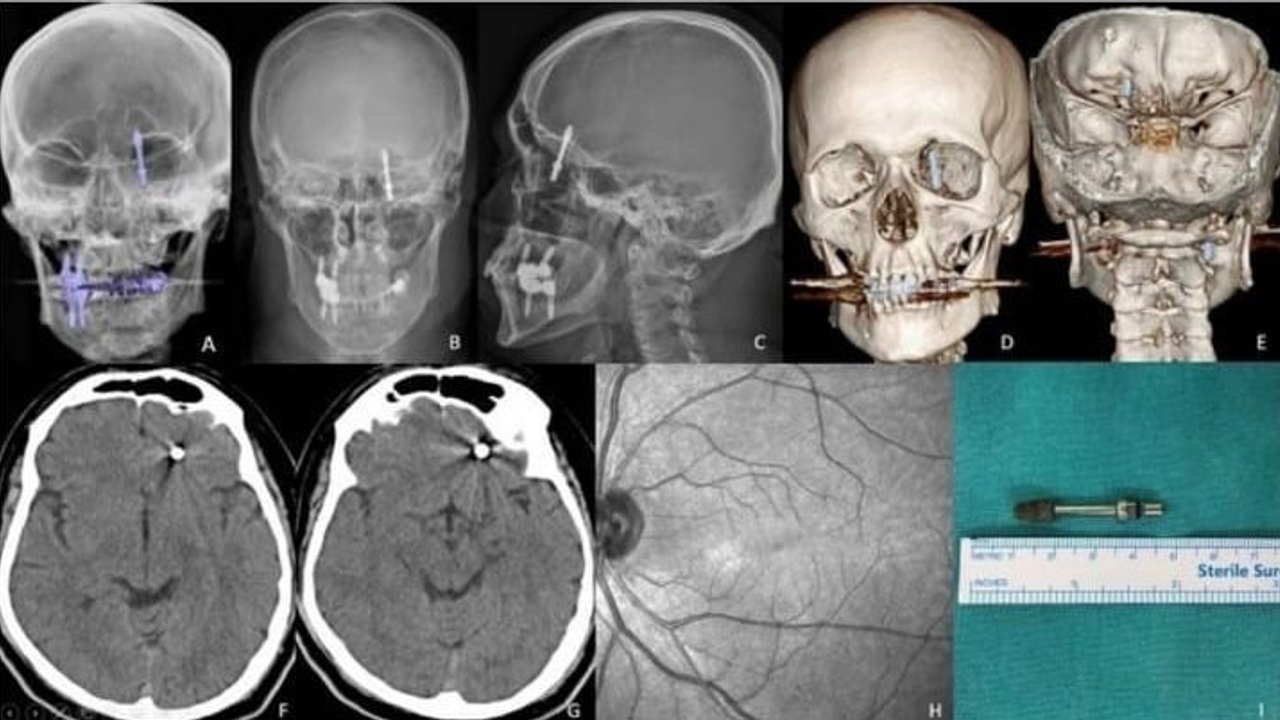

Yılmaz, dişlerinin sallandığı gerekçesiyle kendisine implant tedavisi önerilen Nilüfer’deki özel klinikte muayene oldu. Ancak doktor A.D.’nin hatalı müdahalesi sonucu implant vidası çene kemiğini delerek kafatasına kadar ilerledi. Baygınlık geçiren Yılmaz, kliniğin kendi aracıyla hastaneye kaldırıldı ve tomografide vidanın beynine kadar ulaştığı ortaya çıktı. Saatler süren acil ameliyatla hayatı kurtarıldı.